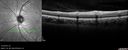

White Retinal Artiole Left eye - Inferotemporal430 views31 year old female with migraines and headaches for the last 12-13 years. Sometimes she gets the visual symptoms with the migraine. When she gets the migraines the pain is on the left side of her head. She gets the problem a few times a month, sometimes more. They usually last 5-6 hours. She has not had a permanent vision change. When she gets a vision change there are spotty dots of blue neon lights in her vision. With her glasses her two eyes are about the same. VA 20/16 in Each Eye     (0 votes)